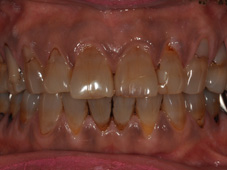

ホワイトニングの例

ケース1:40歳代の女性で、元々の歯の色の濃い方でしたが、2か月のホームホワイトニングと3回のオフィスホワイトニングで、こんなに白くなりました!

⇒

(写真は同じ設定で撮影しており、画像処理を行っていません)